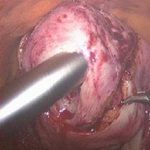

子宫腺肌症,子宫肌瘤,子宫出血等良性疾病,用切除子宫来治疗弊大于利,安太医院签约去病保宫宫腹腔镜手术。